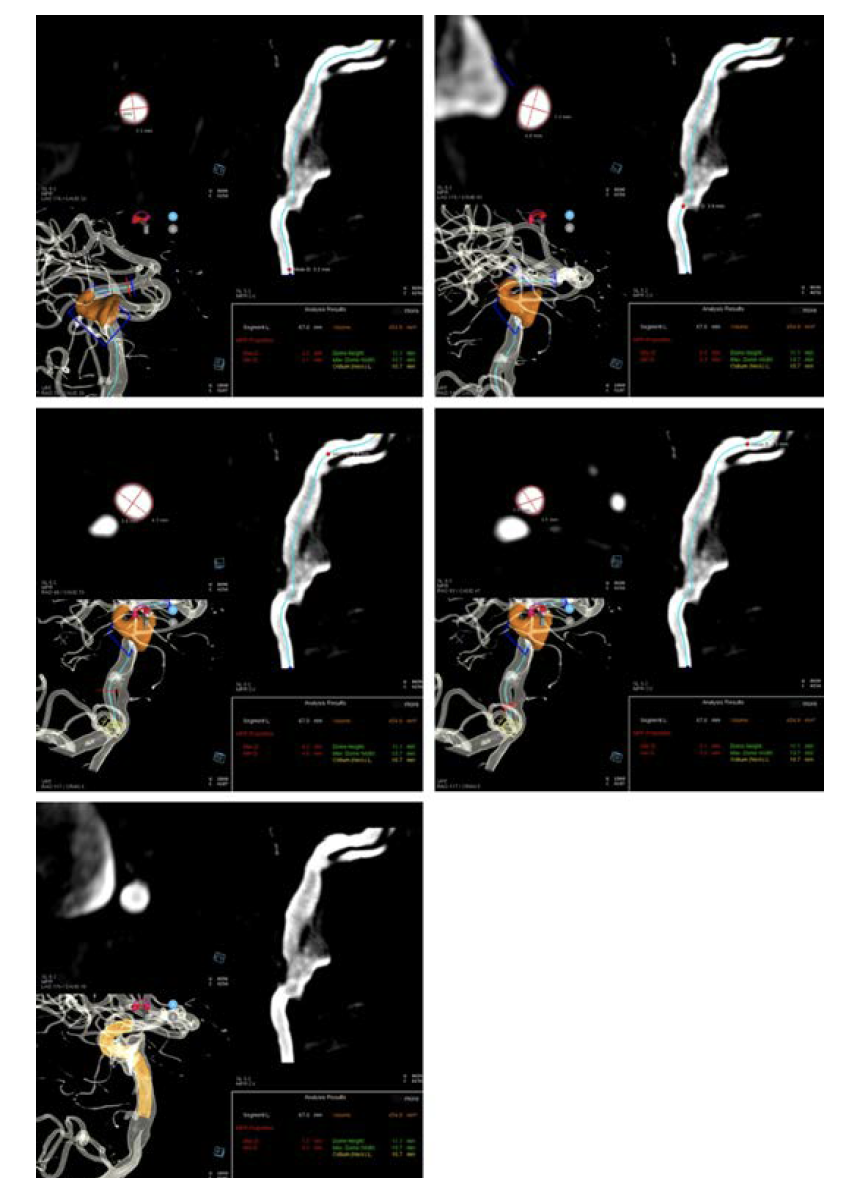

Workflow on the ARTIS icono is exceptional (Figure 1). I start with a biplane angiogram of the entire head. I then do a 4-second DSA 3D acquisition, adjusting the timing of the delay based on the timing of complete opacification on the planar imaging. The 3D reconstruction can then be used to perform syngo Neuro Aneurysm Analysis (Siemens Healthcare AG) to better understand the arterial diameter(s) and start to plan the pipeline construct, both in diameter and length as well as number of devices. The accuracy of the Aneurysm Analysis diameter is excellent and has given us confidence in device diameter selection that we didn’t have previously (Figure 2).

Often, arteries are ovalized and the average diameter provided by the machine has worked very well for us. In addition, the length measured through curvilinear space has enabled us to use shorter devices—almost exclusively 10 and 12 mm. Previously, we would make 1 linear measurement, then move the 3D, make a second measurement, then add 2 mm for margin of error. Often, the stent sizes would end up in the 14- to 16-mm range. Aneurysm Analysis has therefore had a tremendous impact on the way we select devices (Figure 3).

The aneurysm analysis tool was utilized to assess arterial diameters in both the distal and proximal landing zones as well to choose a stent length for the first stent and make an initial plan for the construct (Figure 12).